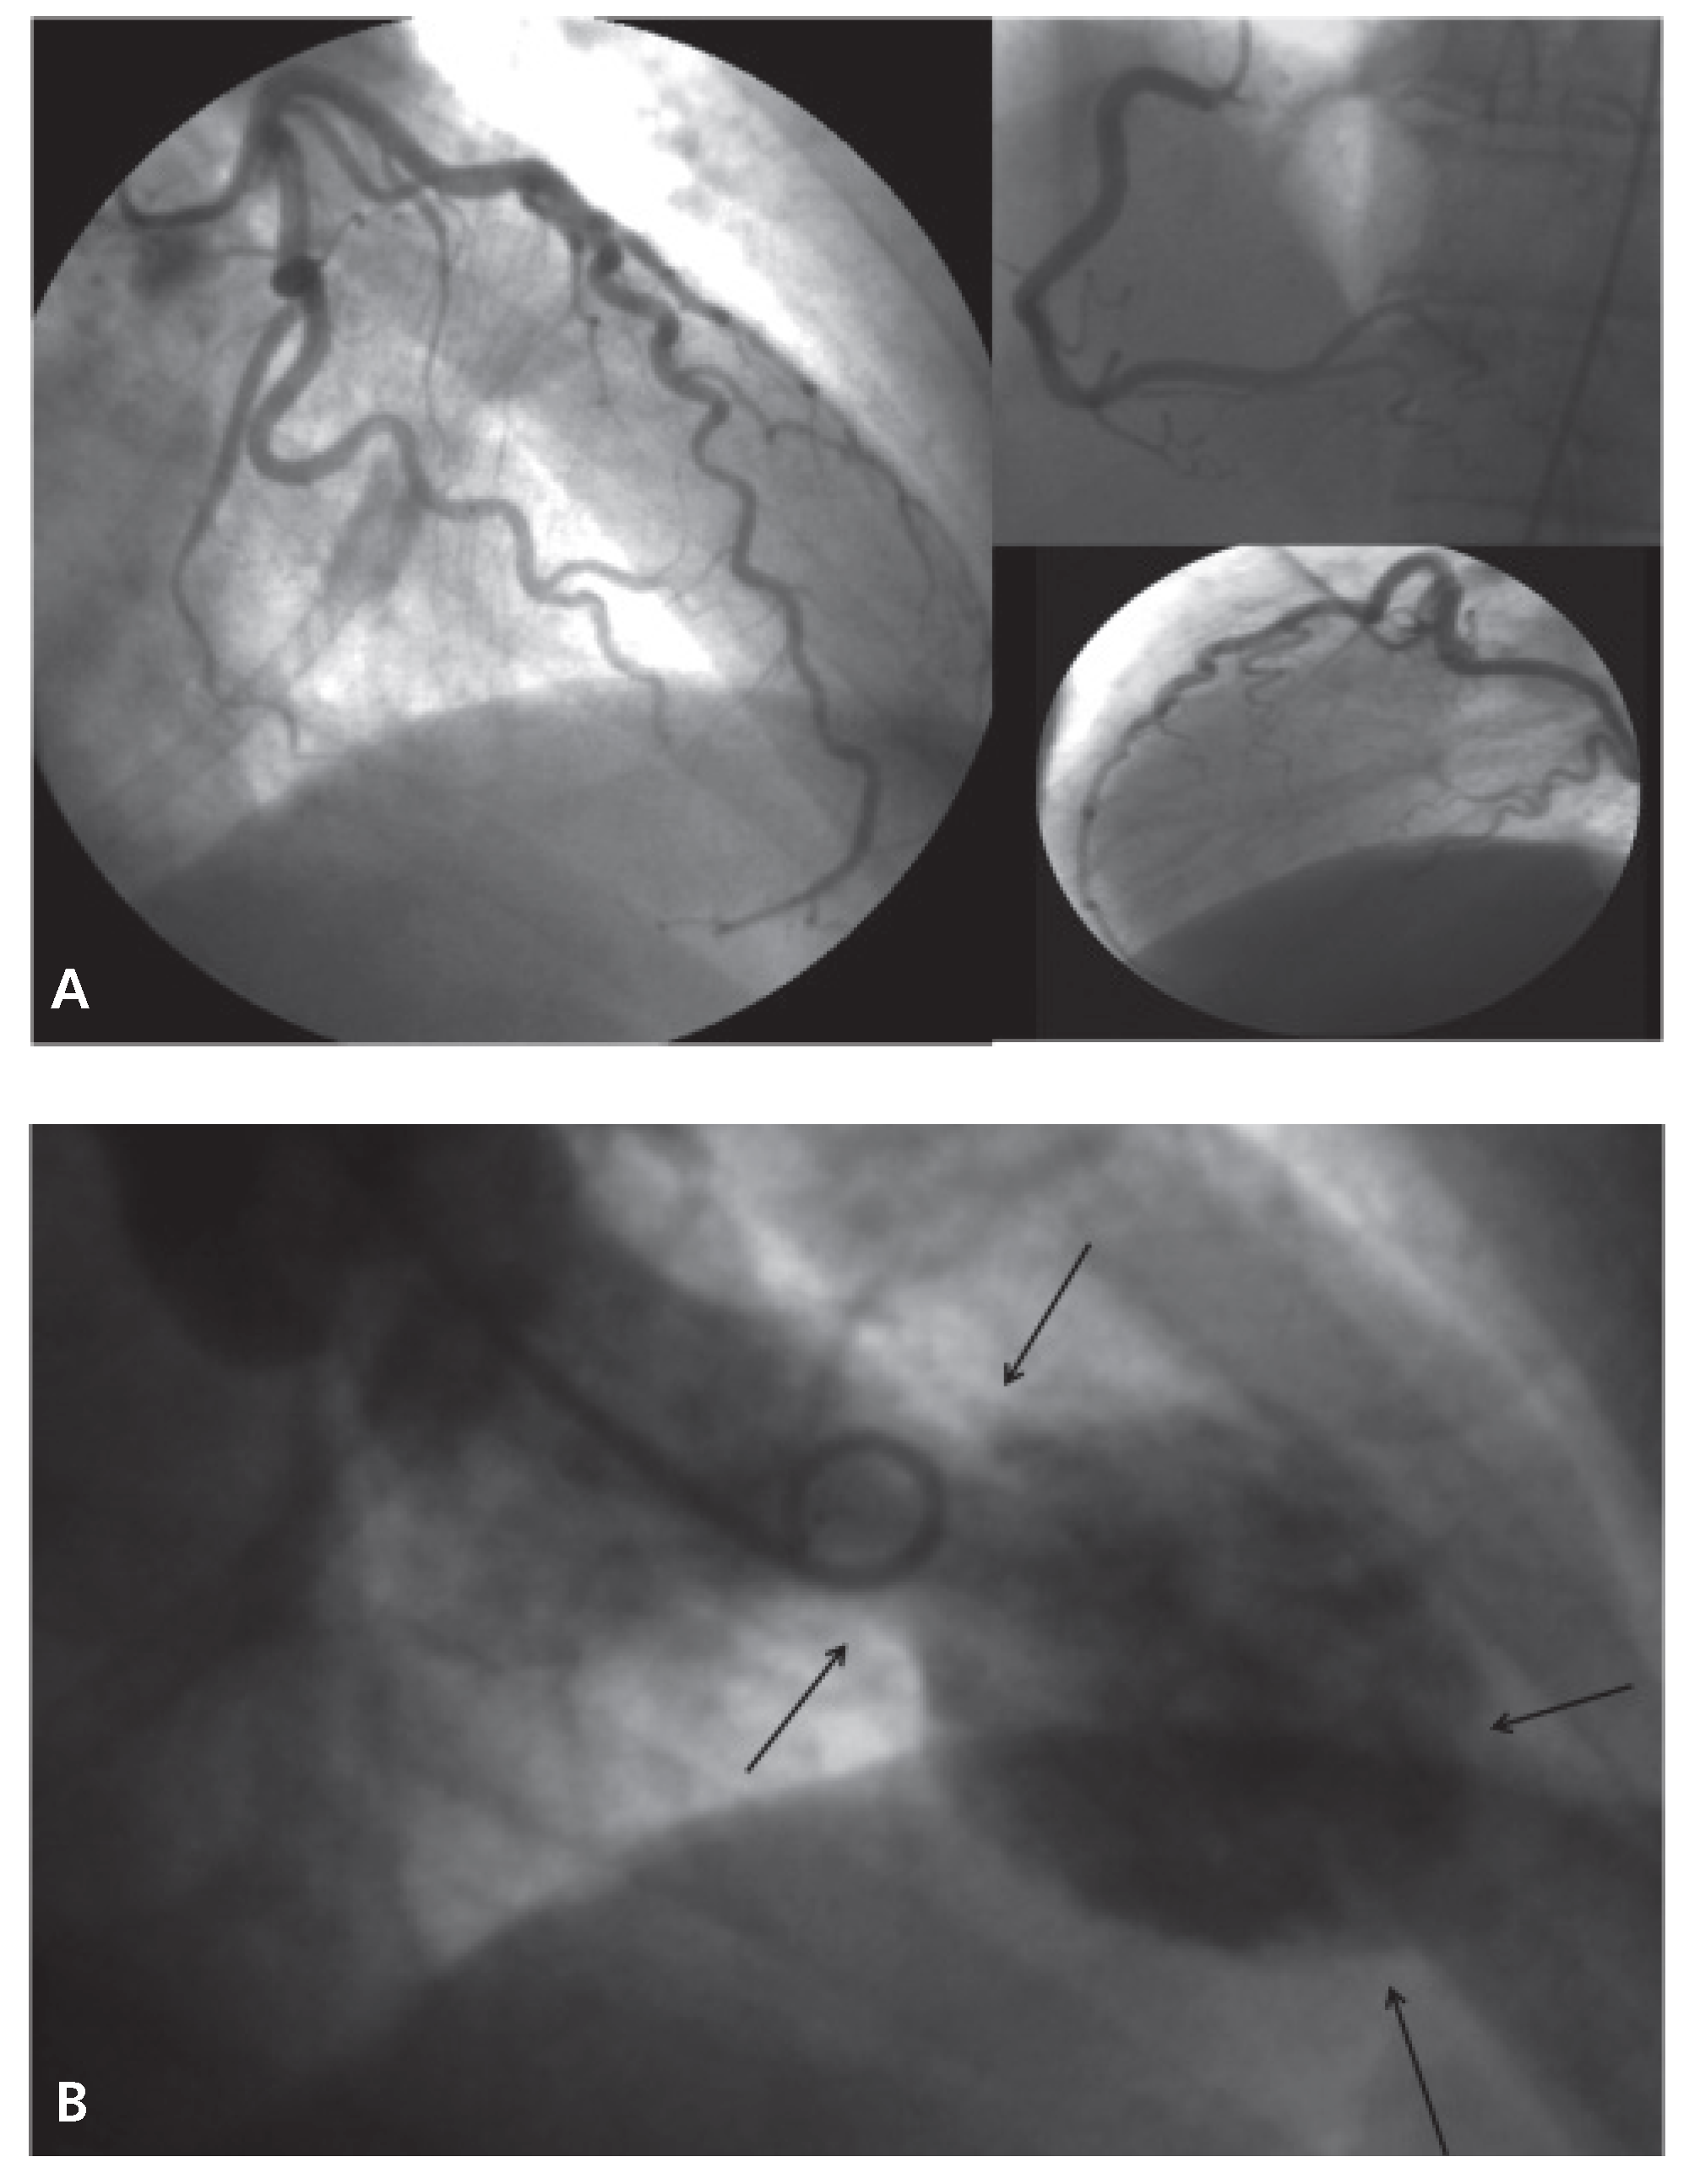

Case Report

Figure 2. A. Urgent coronary angiography showed unobstructed coronary arteries without any features of spasm. B. Left ventriculography showing apical ballooning.